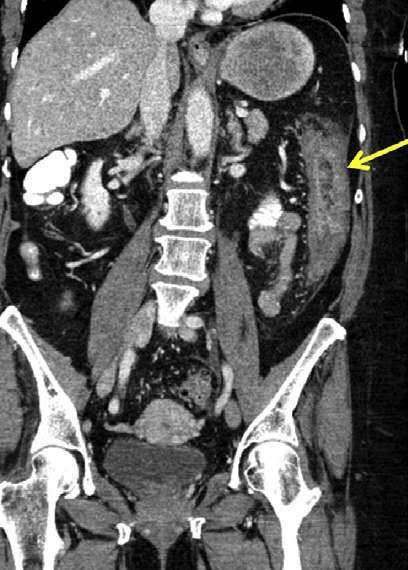

4.缺血性结肠炎:

缺血性结肠炎在左半结肠发生率相对高。平扫CT表现主要为间接征象:如肠壁增厚,肠腔扩张等,直接征象需做增强CT(CTA), 肠系膜动脉或静脉内可见血栓栓子,表现为血管内充盈缺损。肠壁、肠系膜和门脉内积气是急性肠壁缺血坏死的特征性改变。